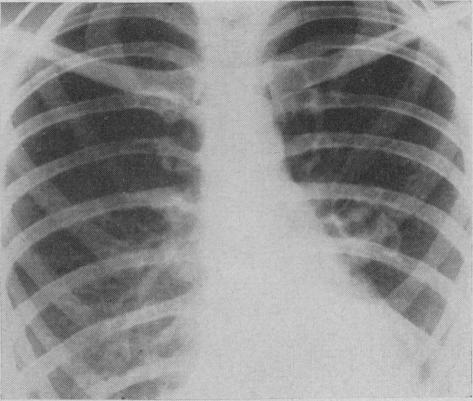

Pulmonary histoplasmosis.

Can Med Assoc J. 1959 Sep 15;81(6):486-8.